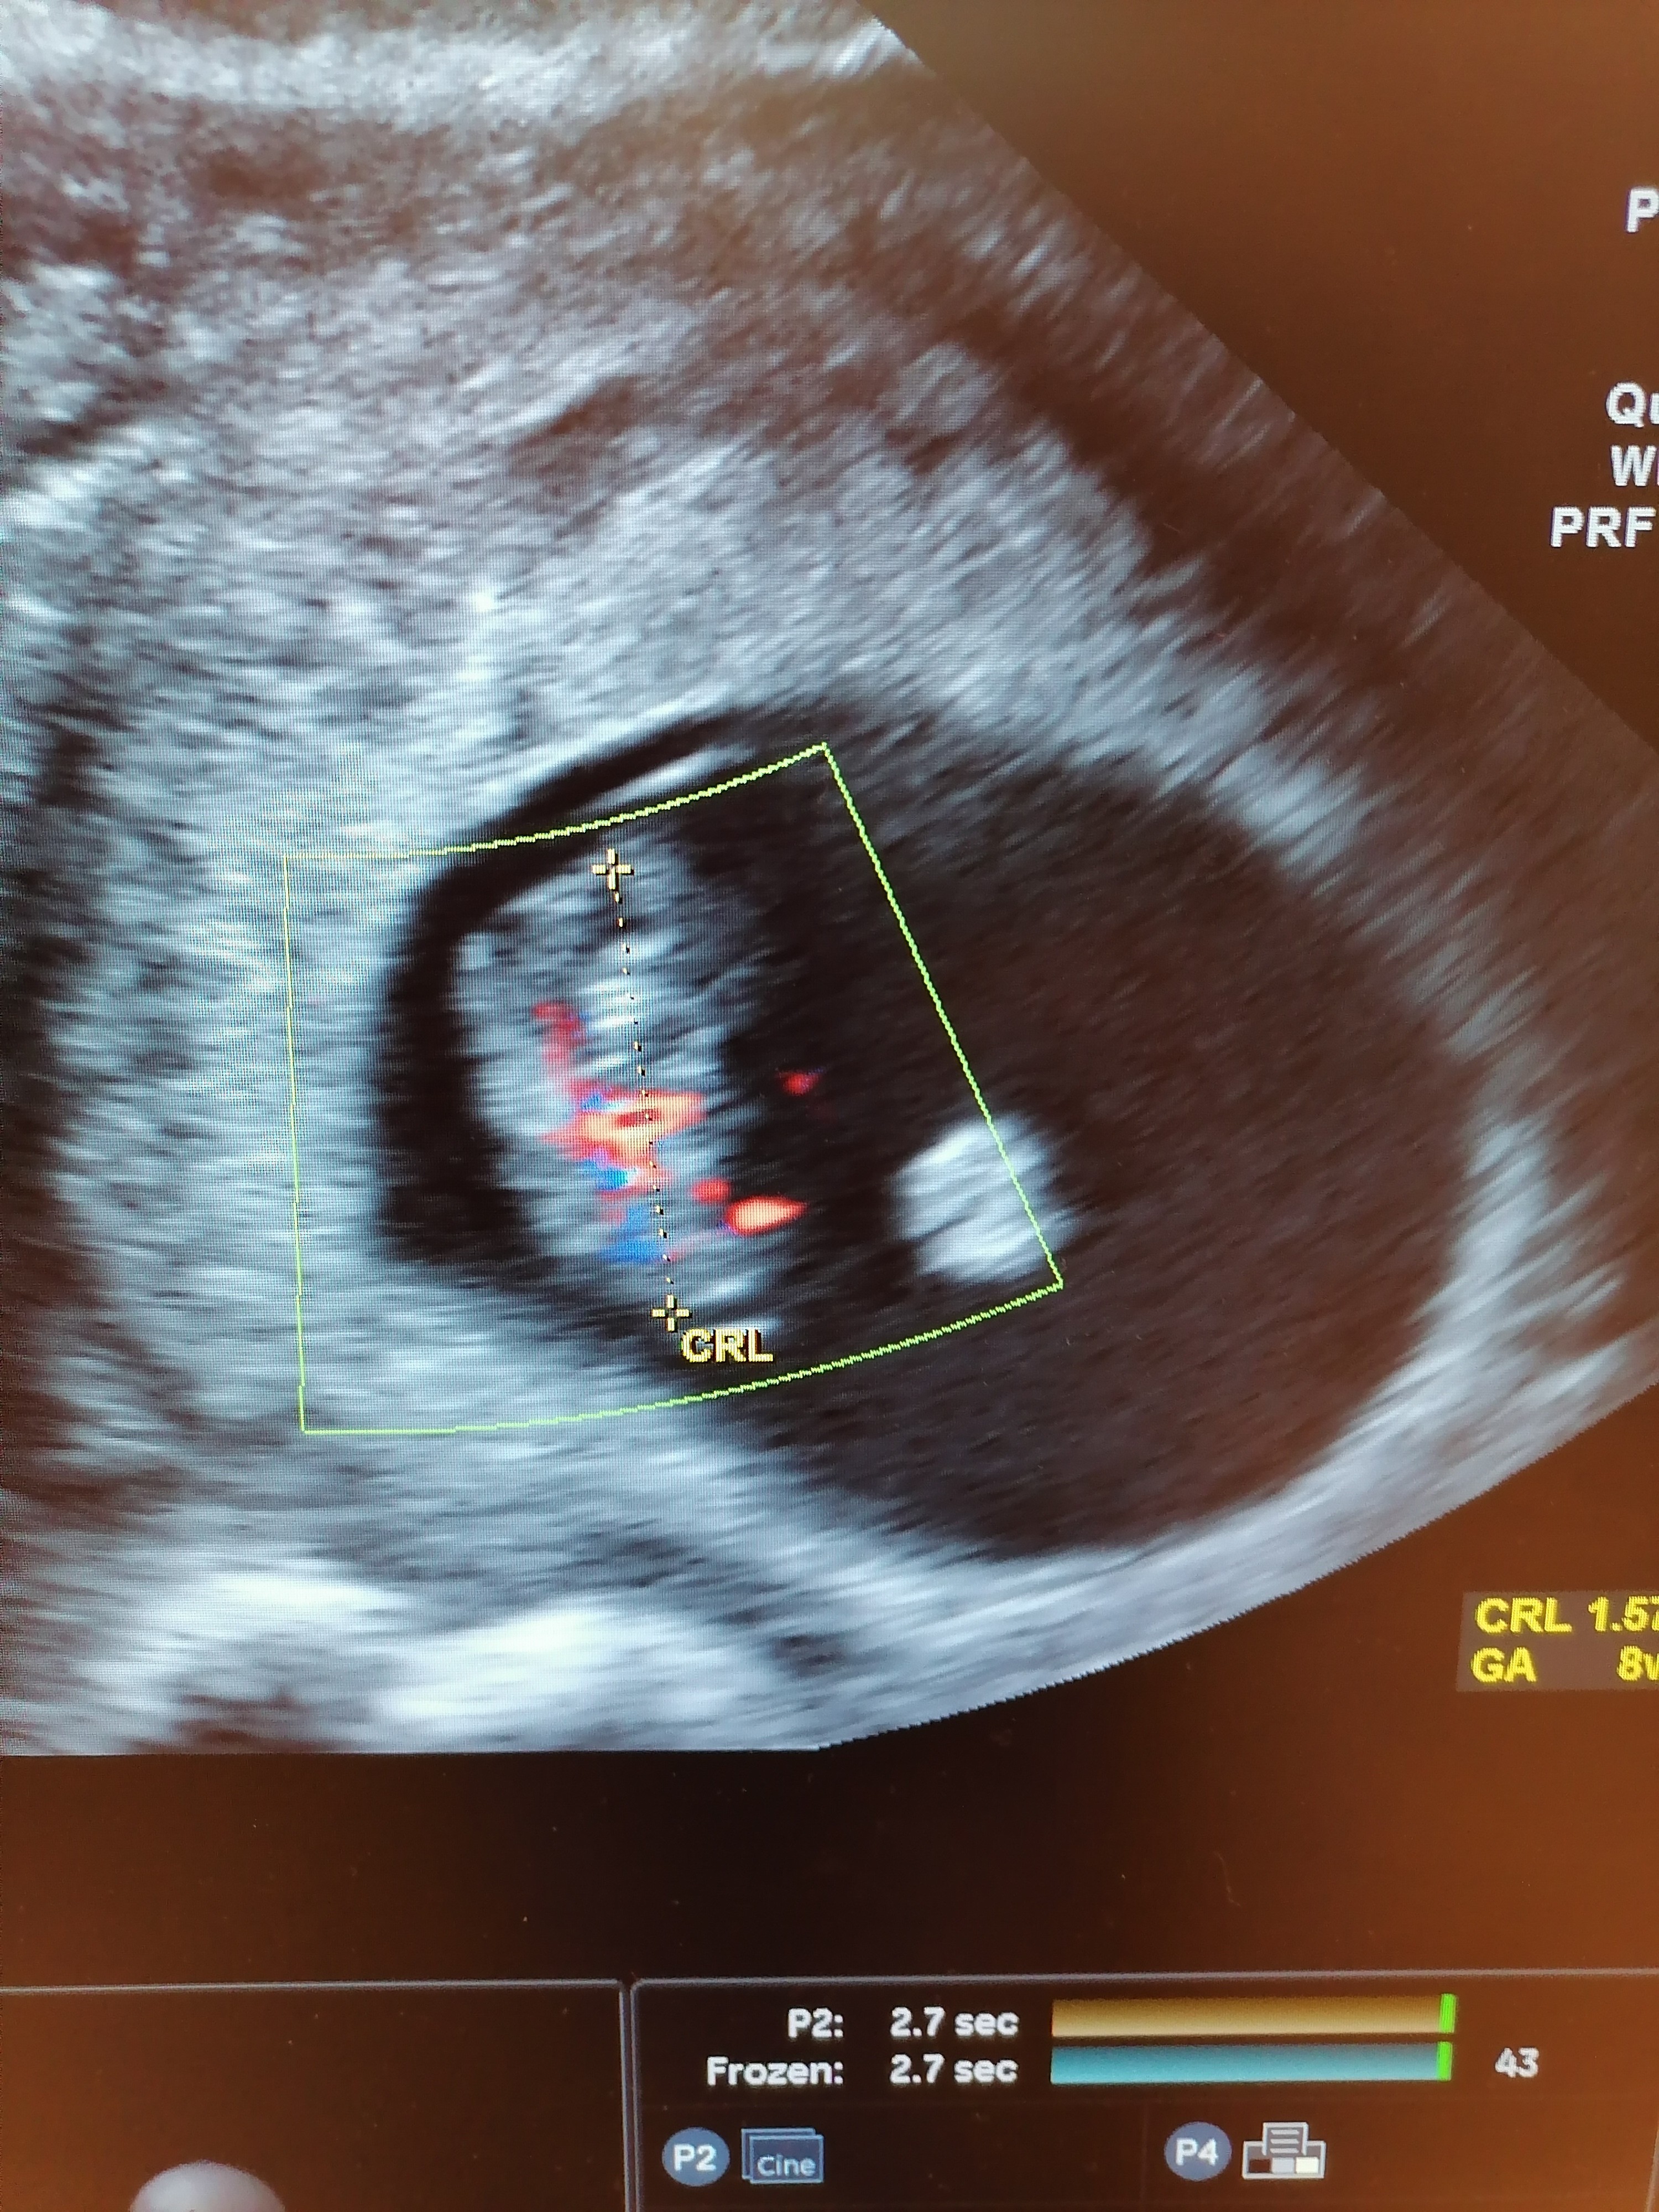

Witam. Dziewczyny byłamu lekarza, jestem teraz w 8 tygodniu ciąży. Dopiero w domu przyjrzałam się zdjęciu usg i zauważyłam kropkę obok zarodka. Czy to możliwe że jest to ciąża bliźniacza jednokosmowkowa? Czy macie może swoje zdjęcia z ciąży blizniaczej dla porownania?

• IMG_20201006_141545.jpg

IMG_20201006_141545.jpg

2,2 MB · Wyświetleń: 595